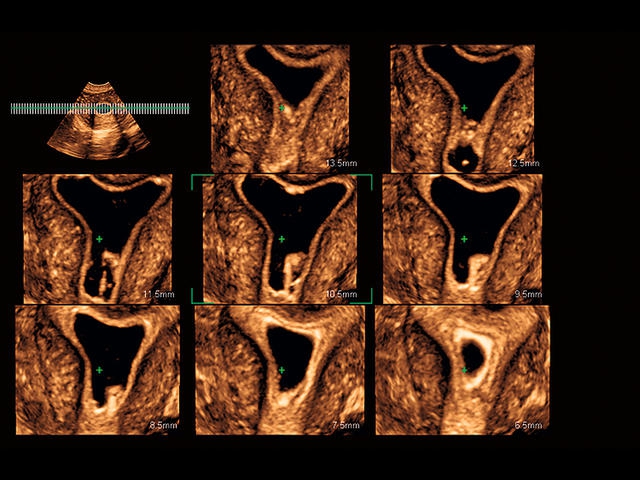

Обновленная версия легендарного УЗ-сканера. Стационарный аппарат экспертного класса Aplio 500 Toshiba NEW, визуализирует анатомические структуры в высоком разрешении. Модель позволяет выявить микрокальцификаты, новообразования, нарушения в работе сердца, сосудов и мышц. Присутствует функция виртуальной эндоскопии, 4D-сканирования, эластометрии тканей, УЗИ с контрастированием. За повышение качества изображения отвечают технологии ApliPure и Superb Microvascular Imaging. Первая задействует возможности пространственного и частотного кодирования, формирует цельный визуальный ряд с сохранением клинических маркеров. Вторая улучшает отображение микрососудистого русла, используя доплеровский эффект. Модель оснащена 21-дюймовым монитором, имеет 4 активных порта. Возможно подключение педиатрических, интраоперационных, лапароскопических и чреспищеводных датчиков.

• MicroPure. Высокотехнологичное решение в области выявления микрокальцификатов – маркеров новообразований злокачественного типа. Маркеры идентифицируются путем изучения затененных изображений целевого участка. Микрокальцификаты отображаются в виде белых пятен.

• D-THI.Режим дифференцированной тканевой гармоники, повышающий качество визуализации глубоко расположенных тканей. Получаемое изображение отличается высокой четкостью, не содержит дефектов в виде «заснеженных» и размытых участков.